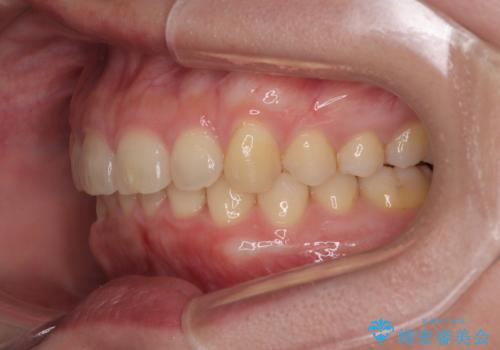

- 下顎前歯が完全に隠れてしまっていることを気にして来院された患者様です。

下顎の臼歯が手前に傾斜していることで咬み合わせが深くなってしまい、下顎前歯が見えないほどに上顎前歯が覆い被さっている状態でした。

下顎臼歯を起き上がらせるためにユーティリティーアーチを使用し、一気に深い咬み合わせを改善することができました。